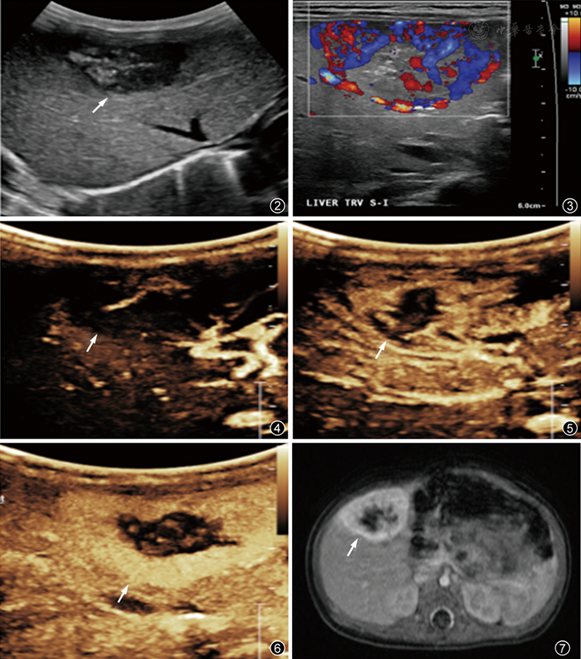

图2~7 患儿女性,39 d,肝右叶快速消退型先天性血管瘤超声声像图及MRI影像图。图2灰阶声像图示肝右叶中央钙化的局灶型肿块(箭头所示);图3彩色多普勒血流成像示肿块内血流信号;图4~7为超声造影动脉相。图4(门脉相)、5(静脉相)、6中箭头示肿块由周边向中央逐渐增强;图7为MRI增强动脉相,与超声造影图像表现类似,肿块呈边缘强化(箭头所示)